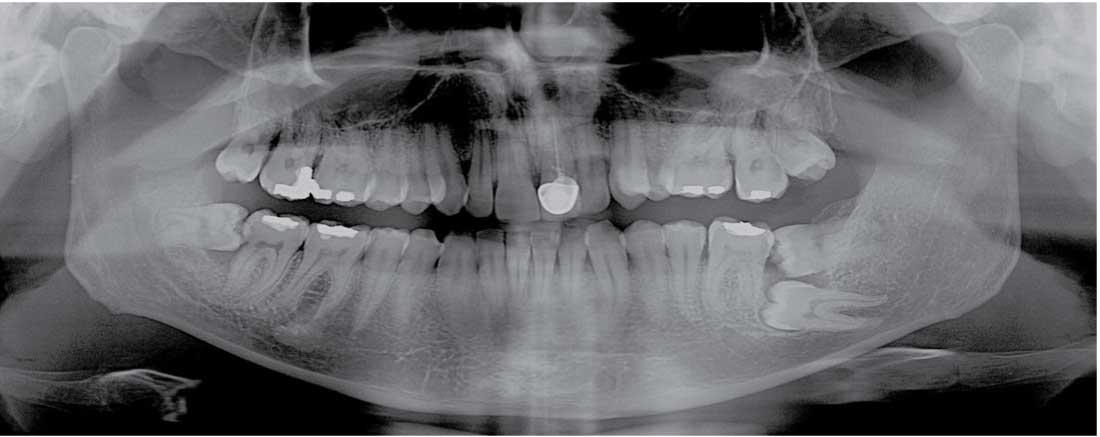

Дентальная галерея: ретинированный зуб клык и его лечение

Раздел: Компас решений